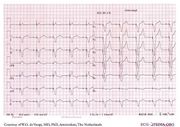

| 09:21, 9 October 2012 | Brugada.jpg (file) |  |

13 KB | 1 | |

| 09:22, 9 October 2012 | Brugada syndrome type1 example3.png (file) |  |

63 KB | 1 | |

| 09:24, 9 October 2012 | Brugada syndrome type1 example4.png (file) |  |

364 KB | 1 | |

| 09:25, 9 October 2012 | Brugada syndrome type1 example5.png (file) |  |

364 KB | 1 | |

| 09:25, 9 October 2012 | Brugada syndrome type1 example1.png (file) |  |

370 KB | 1 | |

| 09:26, 9 October 2012 | Brugada syndrome type2 example1.png (file) |  |

363 KB | 1 | |

| 09:26, 9 October 2012 | Brugada syndrome type1 example2.png (file) |  |

348 KB | 1 | |

| 09:29, 9 October 2012 | Brugada syndrome type2 example2.jpg (file) |  |

677 KB | 1 | |

| 09:31, 9 October 2012 | Brugada syndrome type1 example6.jpg (file) |  |

970 KB | 1 | |